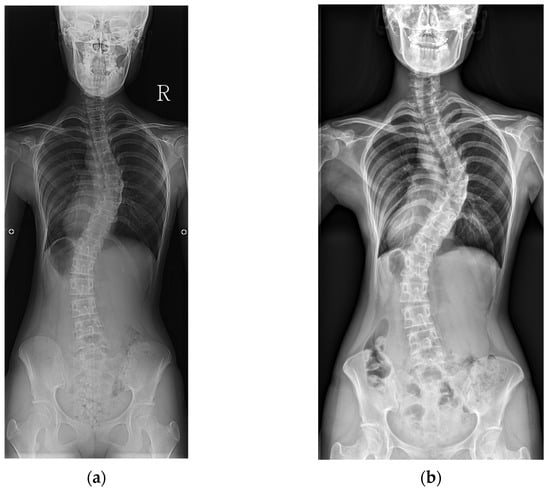

Representative cases from the no-progression and progression groups are shown in Figure 1 and Figure 2.

Figure 2. An example of curve progression. (a) A baseline radiograph of a 14-year-old female patient with Risser stage IV and a Cobb angle of 44°. (b) A final radiograph at age 26, showing Risser stage V and a Cobb angle of 62°.